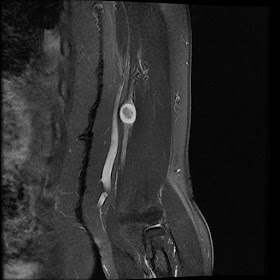

Peroneus Quartus

Peroneus quartus muscle and tendon.

Prevalence: 12-22%

Originates at the distal lateral portion of the fibula and descends medial and posterior to the peroneal tendons.

Insertion is variable and includes the retrotrochlear eminence of the calcaneus, the phalanx or the metatarsal bone of the fifth toe, the peroneal tendons, the lateral retinaculum of the ankle, and the cuboid bone.

Also: incidental Achilles Tendinosis